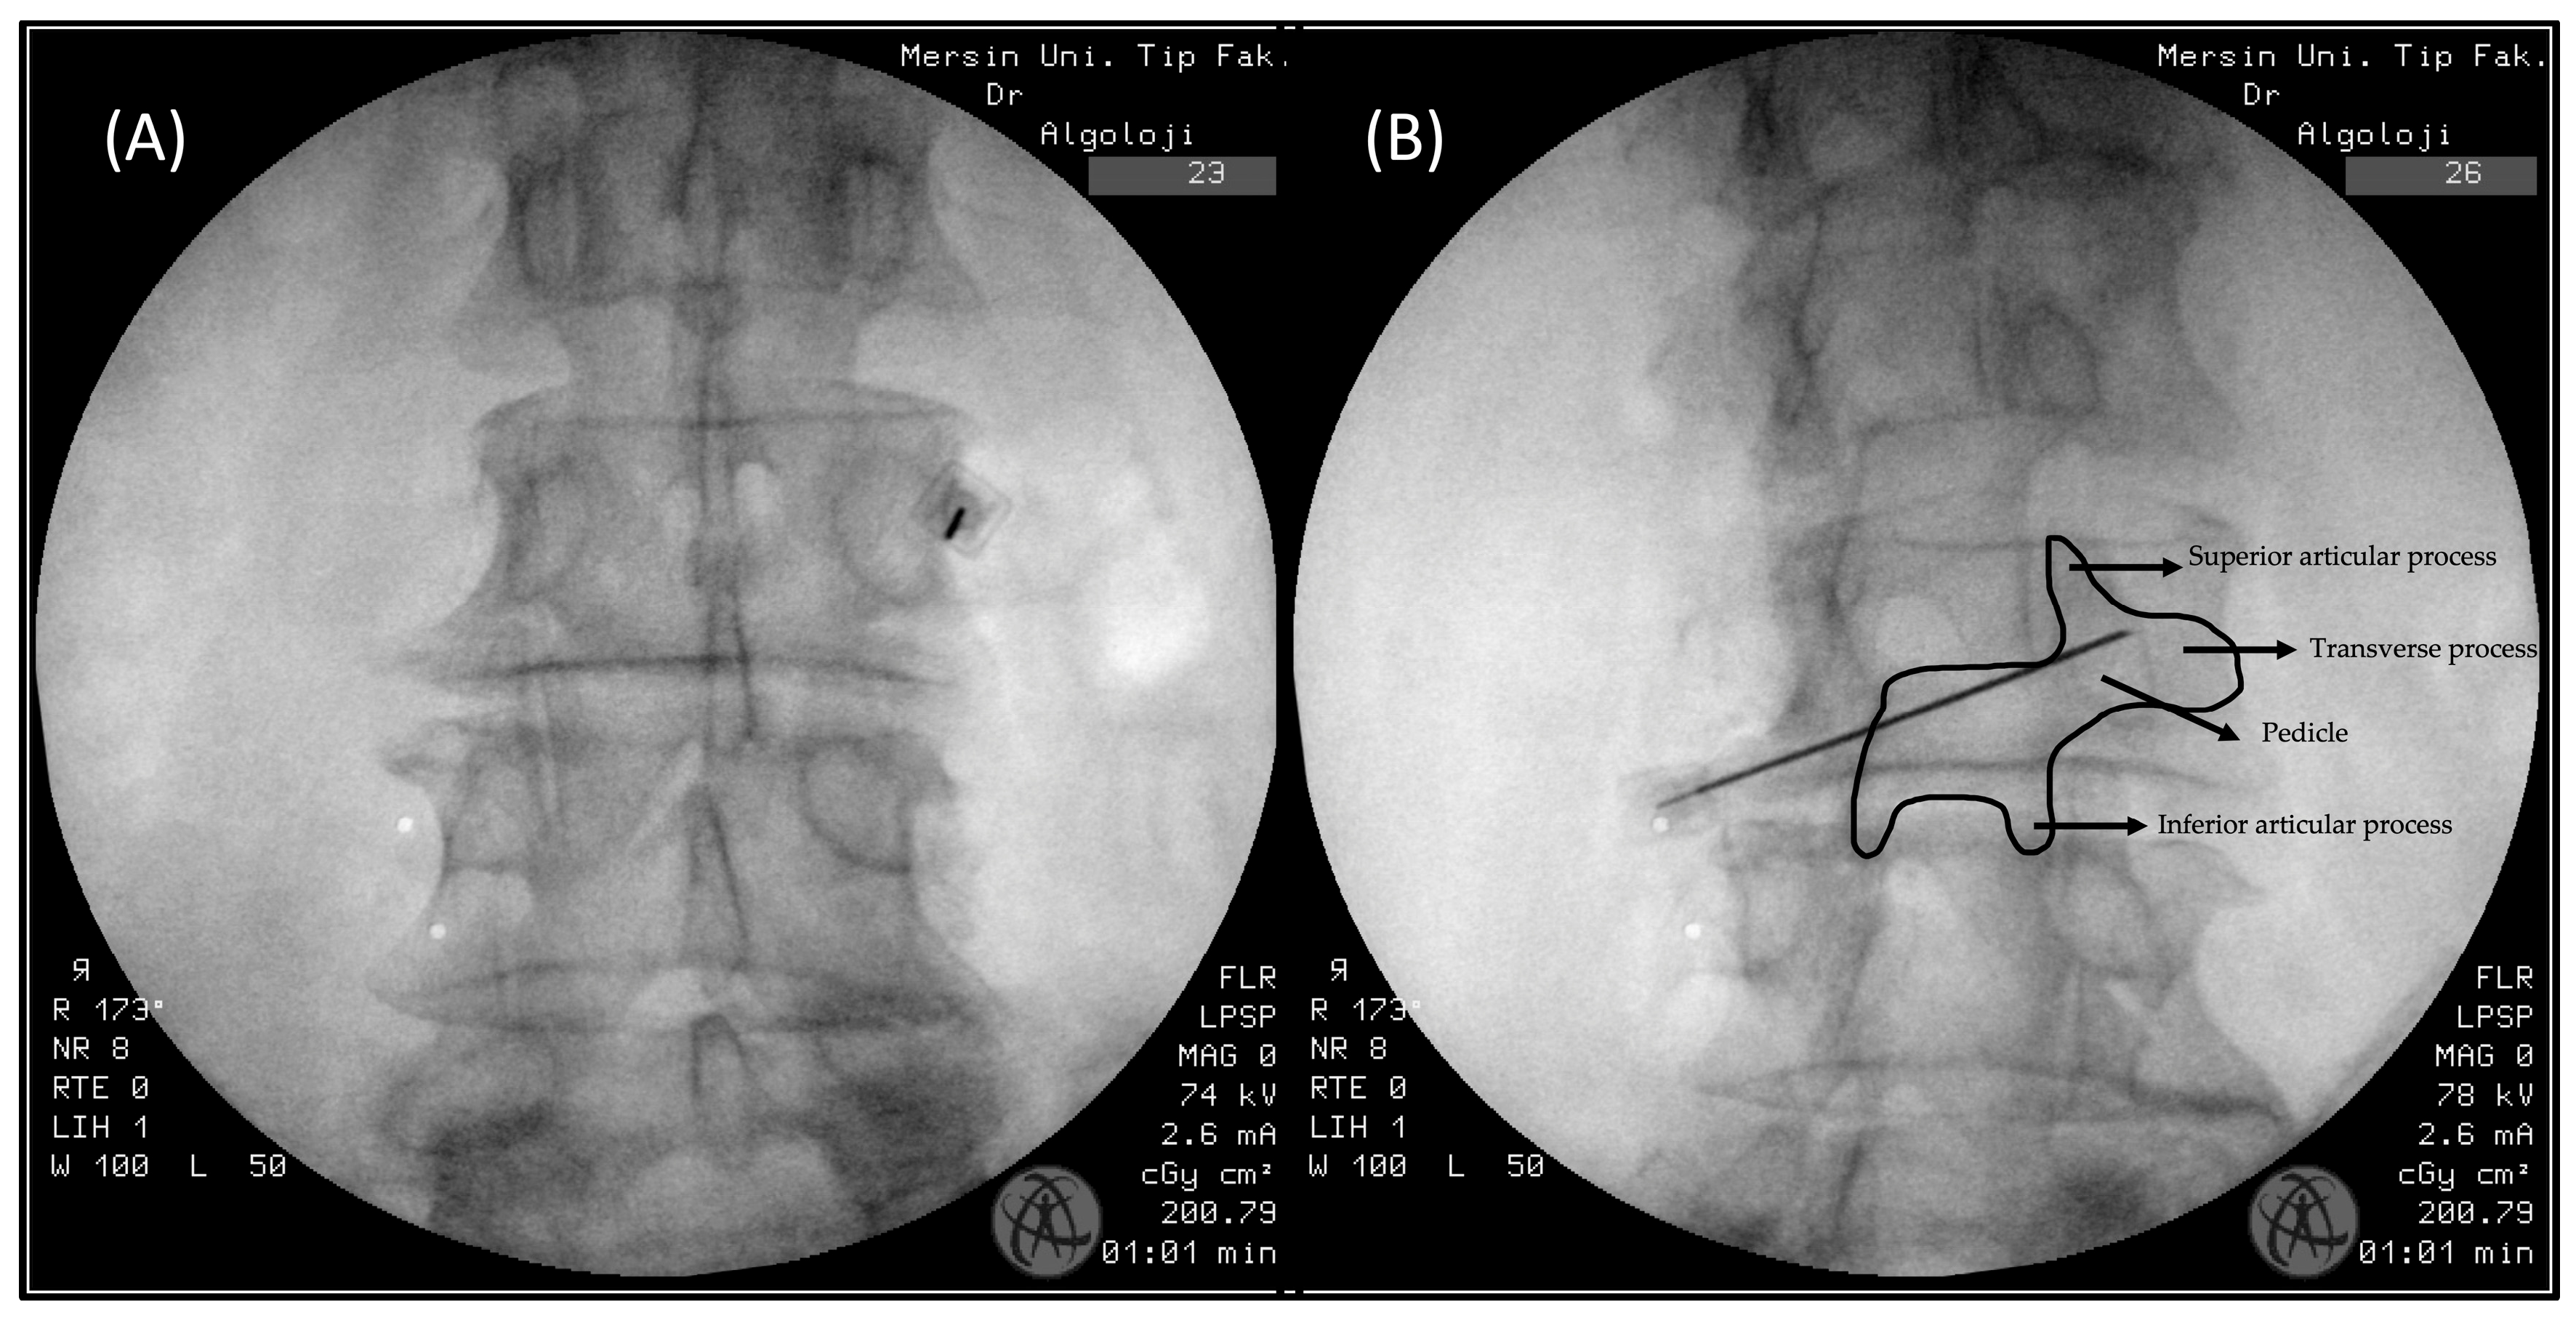

In this technique, patients are also positioned prone. However, unlike the oblique technique, the fluoroscope remains in a direct AP position. The target area is the medial part of the transverse process, near the pedicle, which corresponds to the same region identified by the Scottie dog in the oblique technique [10] (Figure 3A,B).

Figure 3. (A): Anterior–posterior (AP) technique FMBB fluoroscopy view. (B) This image was taken to ensure that the needle was in the targeted “Scottie dog” area.